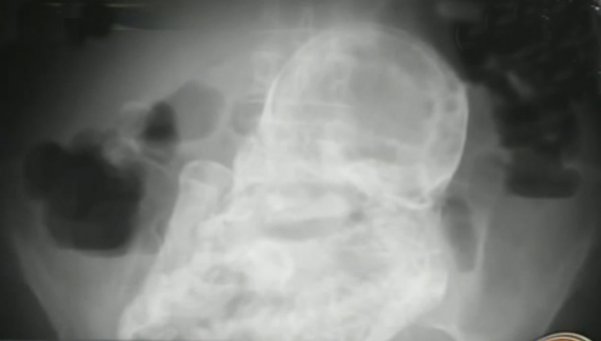

할머니를 진단한 의사는 “초음파검사에선 나오지 않았지만 엑스레이에선 죽은 태아의 얼굴, 팔, 다리, 척추와 갈비뼈 등이 비교적 선명하게 보였다.”고 말했다. 발달 상태를 볼 때 태아는 임신 20~28주 사이 사망한 것으로 추정된다고 덧붙였다.